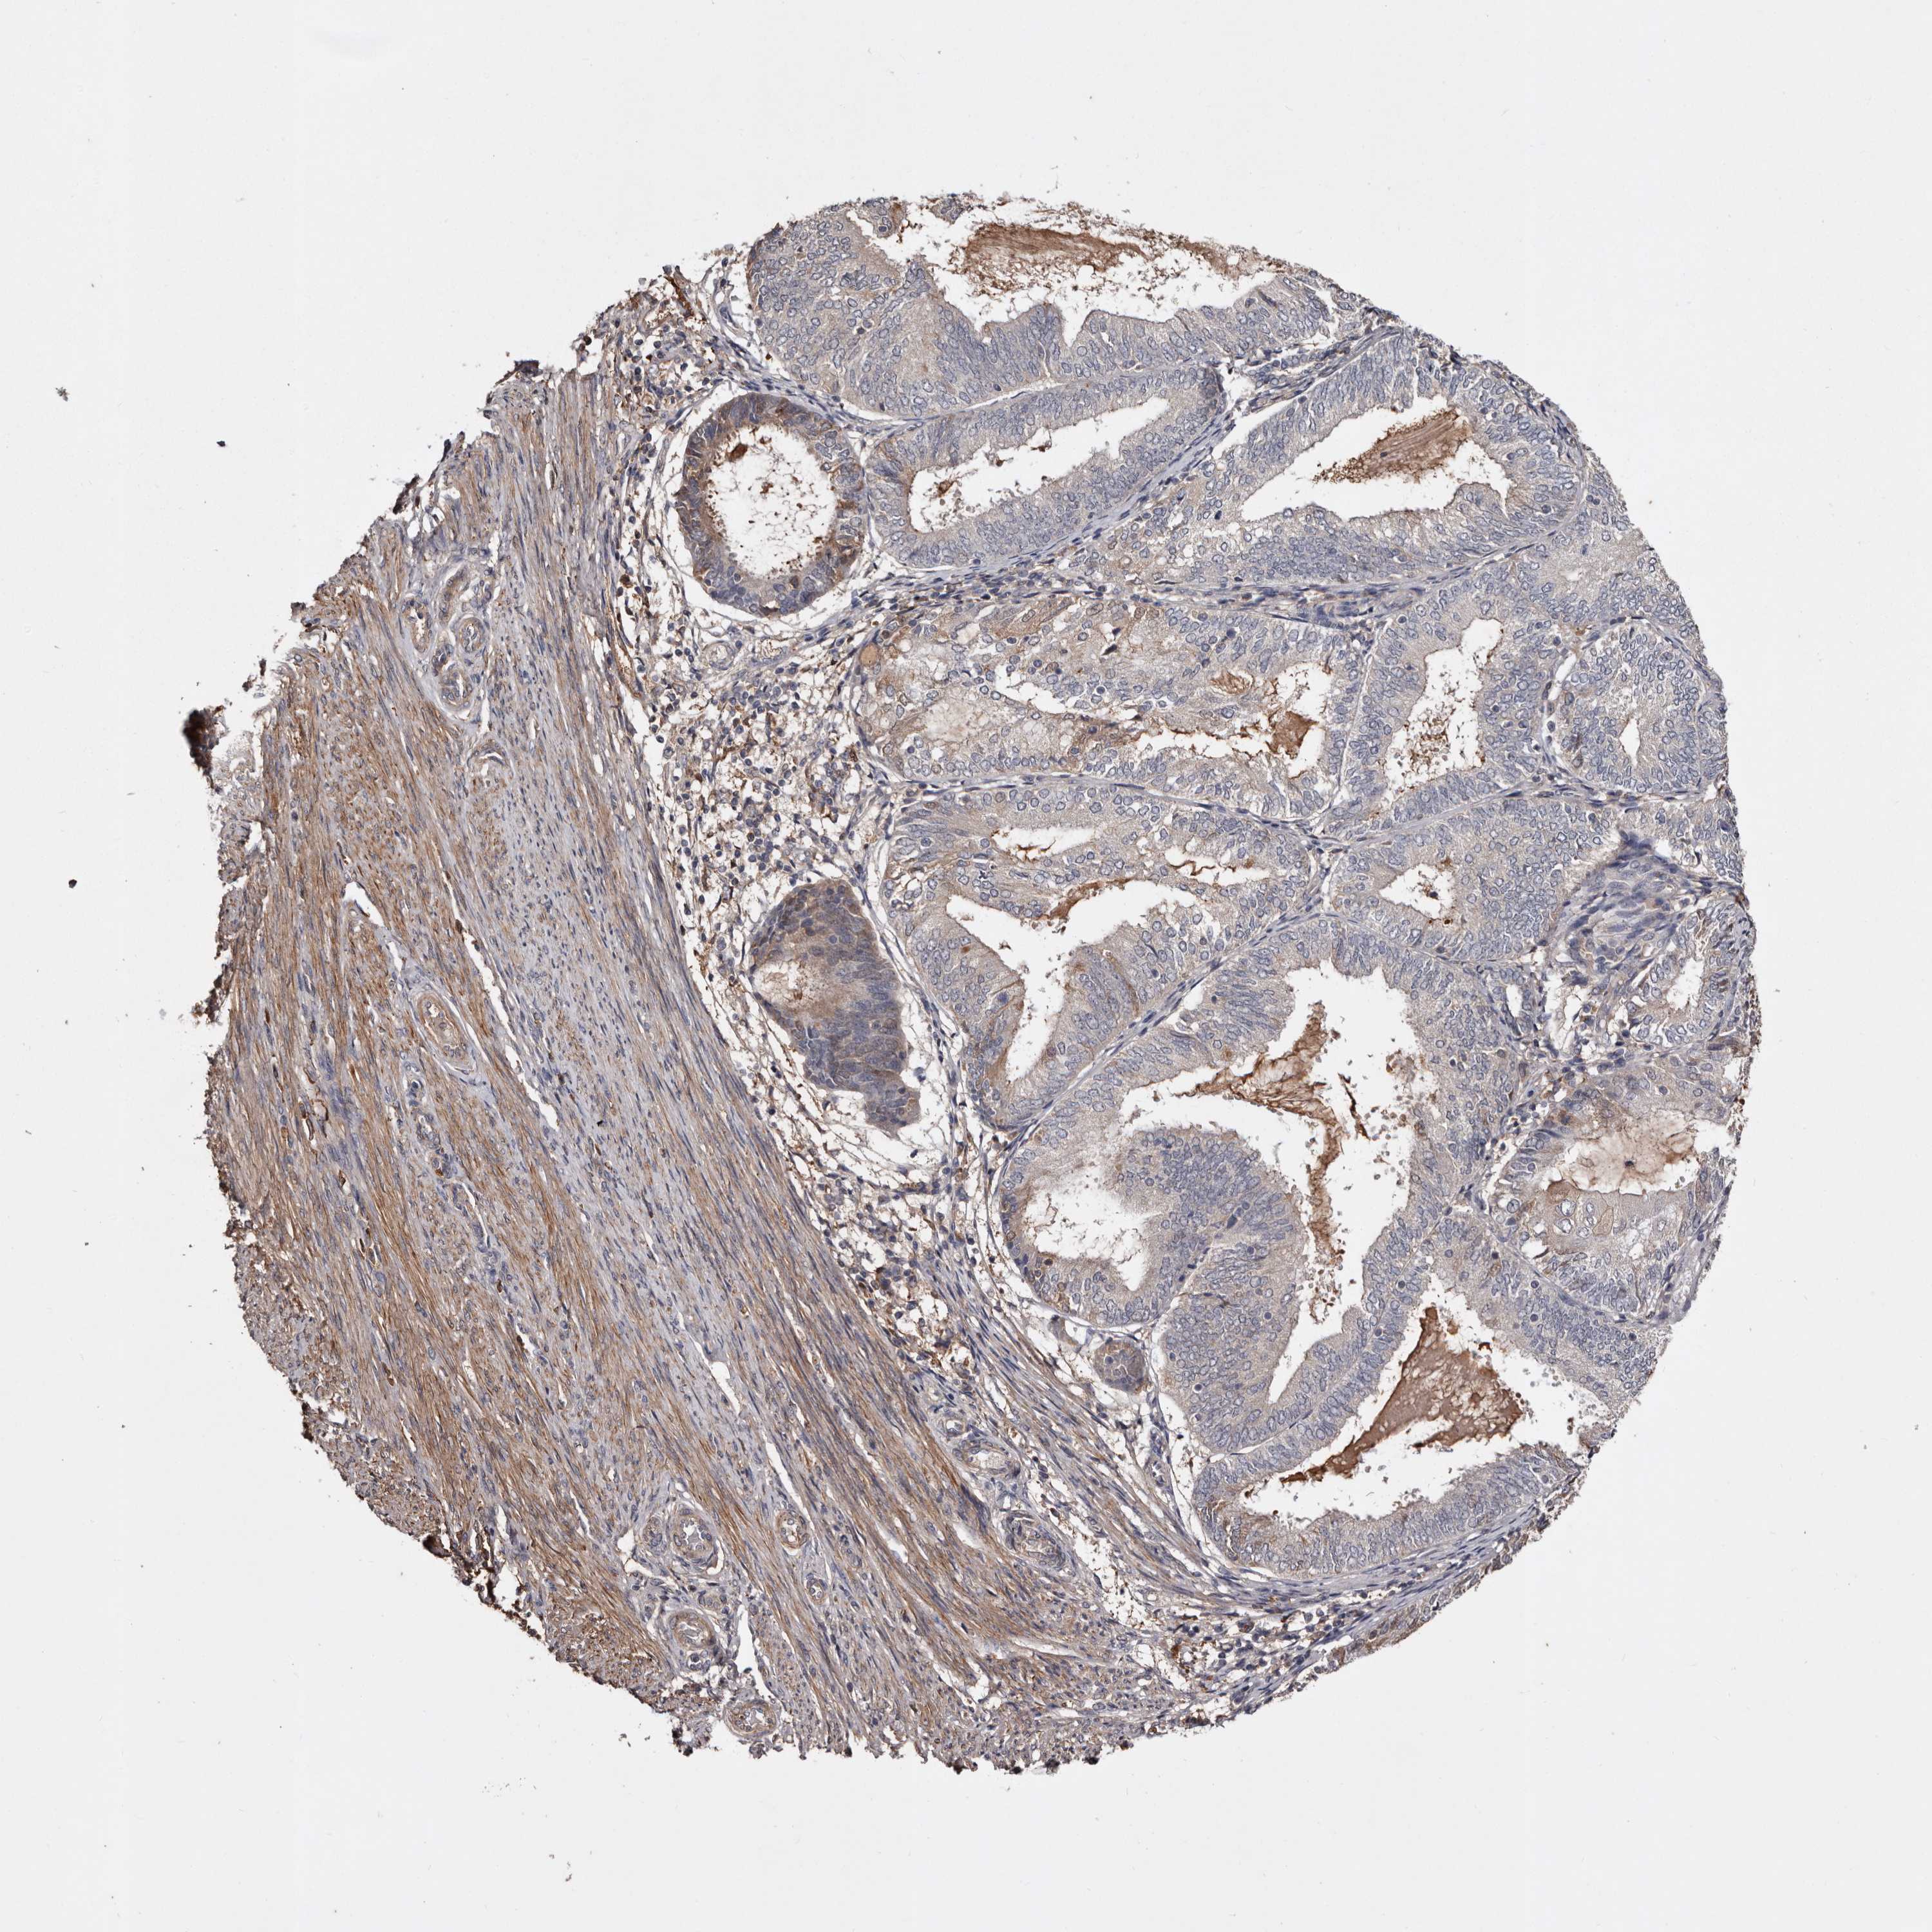

ENDOMETRIAL CANCER - Protein expressioni

A mouse-over function shows sample information and annotation data. Click on an image to view it in a full screen mode. Samples can be filtered based on level of antibody staining by selecting one or several of the following categories: high, medium, low and not detected. The assay and annotation is described here.

Note that samples used for immunohistochemistry by the Human Protein Atlas do not correspond to samples in the TCGA dataset.

Antibody stainingi

Antibody staining in the annotated cell types in the current human tissue is reported as not detected, low, medium, or high, based on conventional immunohistochemistry profiling in selected tissues. This score is based on the combination of the staining intensity and fraction of stained cells.

Each image is clickable and will lead to virtual microscopy that enables deeper exploration of all samples and also displays staining intensity scores, fraction scores and subcellular localization as well as patient and tissue information for each sample.

Antibody HPA026863

Antibody CAB011705

Staining

High

Medium

Low

Not detected

Intensity

Strong

Moderate

Weak

Negative

Quantity

>75%

75%-25%

<25%

None

Location

Nuclear

Cytoplasmic/membranous

Cytoplasmic/membranous,nuclear

Adenocarcinoma, NOS

Adenocarcinoma, metastatic, NOS